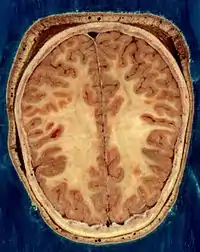

Horizontal section of the head of an adult female, showing skin, skull, and brain with grey matter (brown in this image) and underlying white matter

The vertebrate nervous system can also be divided into areas called gray matter and white matter.[18] Gray matter (which is only gray in preserved tissue, and is better described as pink or light brown in living tissue) contains a high proportion of cell bodies of neurons. White matter is composed mainly of myelinated axons, and takes its color from the myelin. White matter includes all of the nerves, and much of the interior of the brain and spinal cord. Gray matter is found in clusters of neurons in the brain and spinal cord, and in cortical layers that line their surfaces. There is an anatomical convention that a cluster of neurons in the brain or spinal cord is called a nucleus, whereas a cluster of neurons in the periphery is called a ganglion.[19] There are, however, a few exceptions to this rule, notably including the part of the forebrain called the basal ganglia.[20]